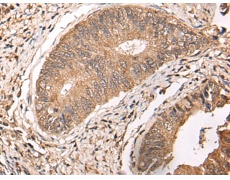

IHC positive control: |

Human colorectal cancer |

IHC Recommend dilution: |

25-100 |